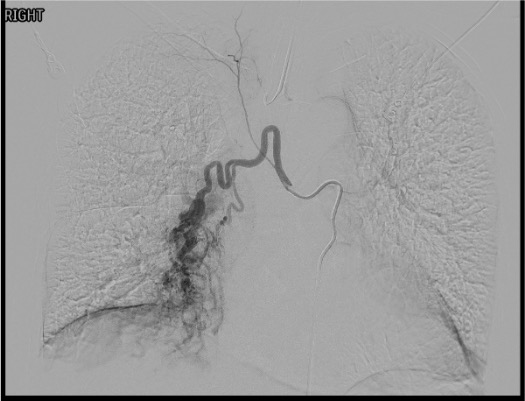

Angiographic Assessment

Embolization

Search for Non-Bronchial Systemic Supply

Completion Angiography

ICBT Identification

- Right intercostobronchial trunk is the most common right-sided bronchial artery configuration

- Arises from the right posterolateral aorta

- Gives off the right bronchial artery + right intercostal artery

- The intercostal branch may supply the anterior spinal artery — always check

Spinal Artery Hairpin Sign

- Small branch coursing medially toward the spinal canal

- Makes a sharp “hairpin” turn as it joins the anterior spinal artery

- If seen: STOP — do NOT embolize that vessel from this position

- Advance microcatheter distal to spinal artery origin or abandon vessel